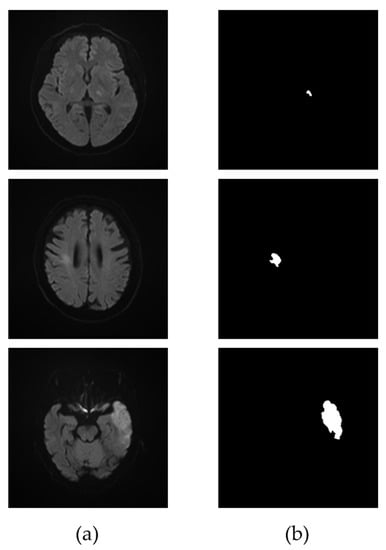

3.2. Extraction of the Infarcted Regions